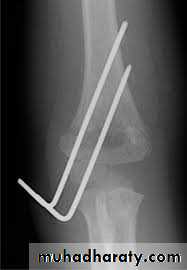

Upper limb

Fall on out stretched hand

xray